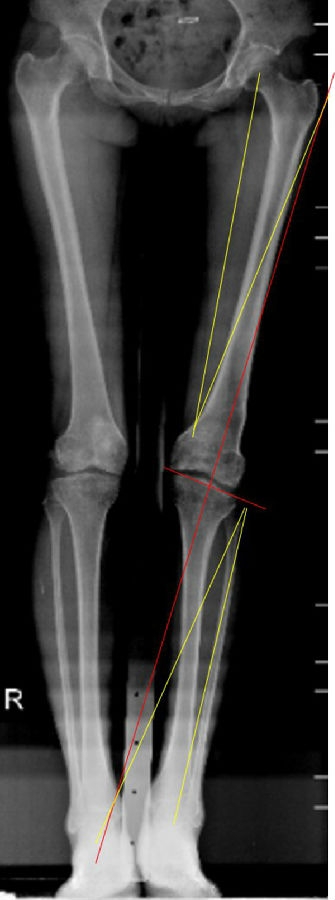

术前计划:

股骨胫骨双截骨矫正下肢内翻畸形;

以关节线为参考,设定下肢目标力线;

避免单纯胫骨侧或股骨侧大角度矫正下肢畸形;

截骨后关节线不发生内倾倾斜,剪切力大;

拟行股骨外侧闭合楔+胫骨内侧闭合楔。

双下肢关节外畸形(畸形来源于股骨侧及胫骨侧)——LDFA:100°*,MPTA:102。°